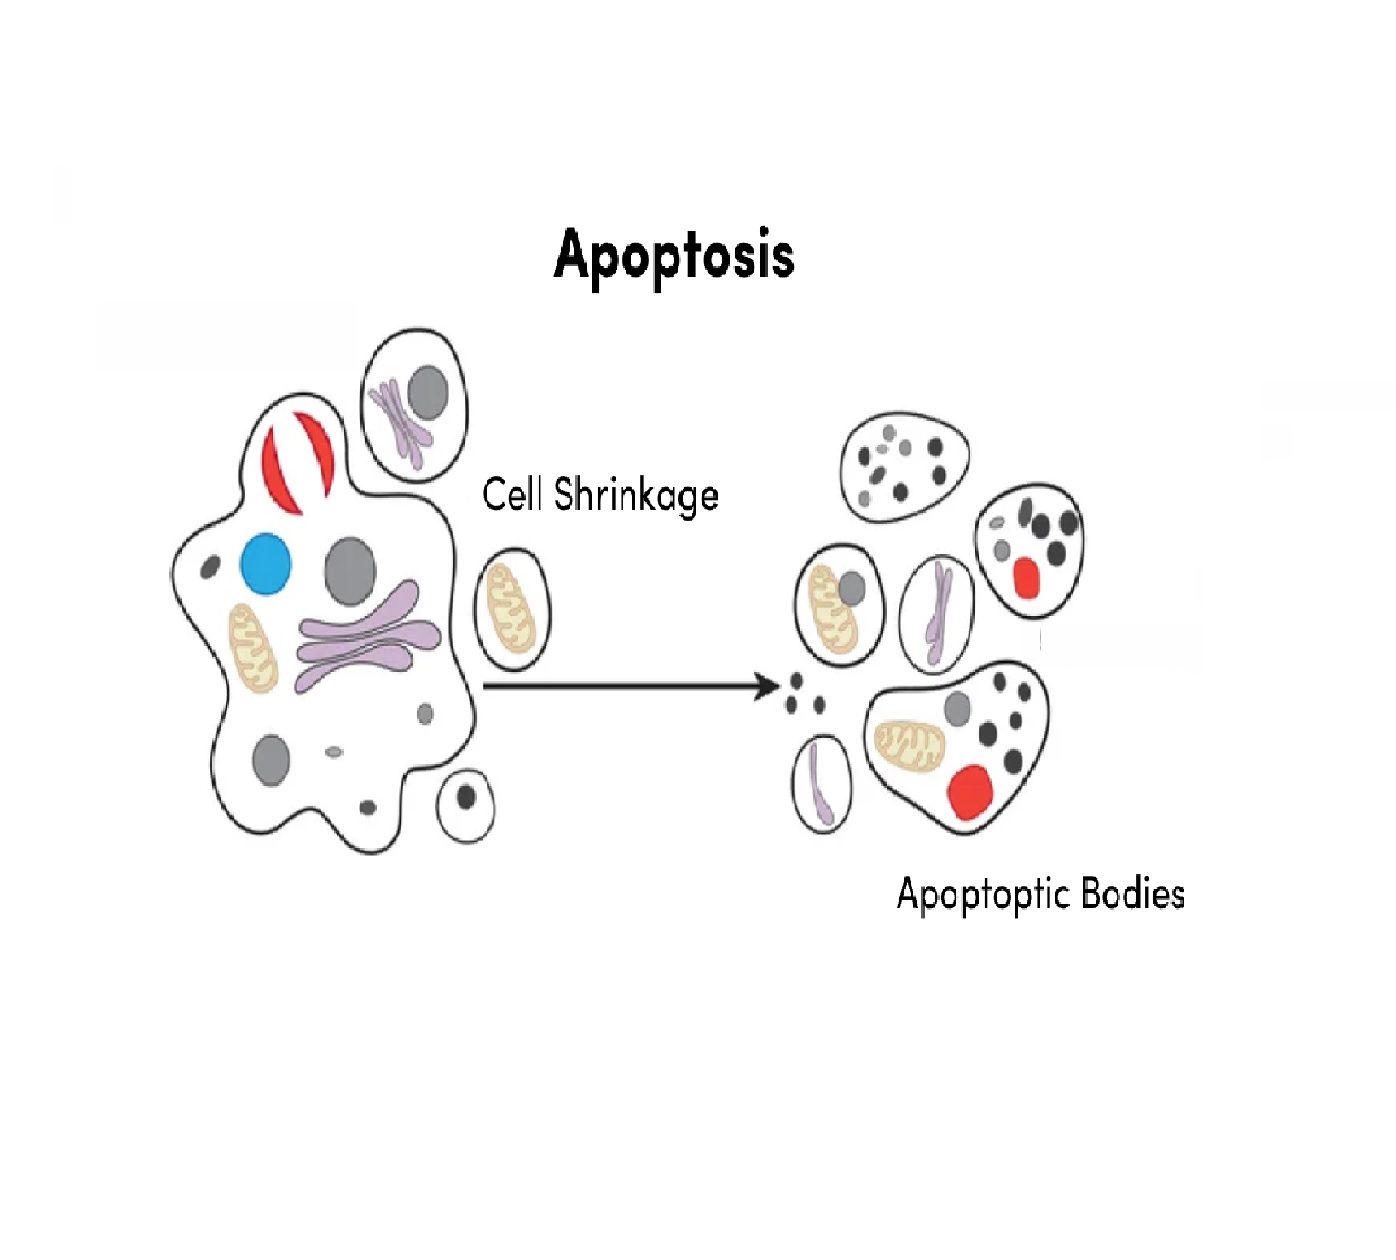

کیت های انداره گیری توتال پروتئین، اپوپتوز، مارکر پروتئینی، ستون خالص سازی پروتئین

- آپوپتوز